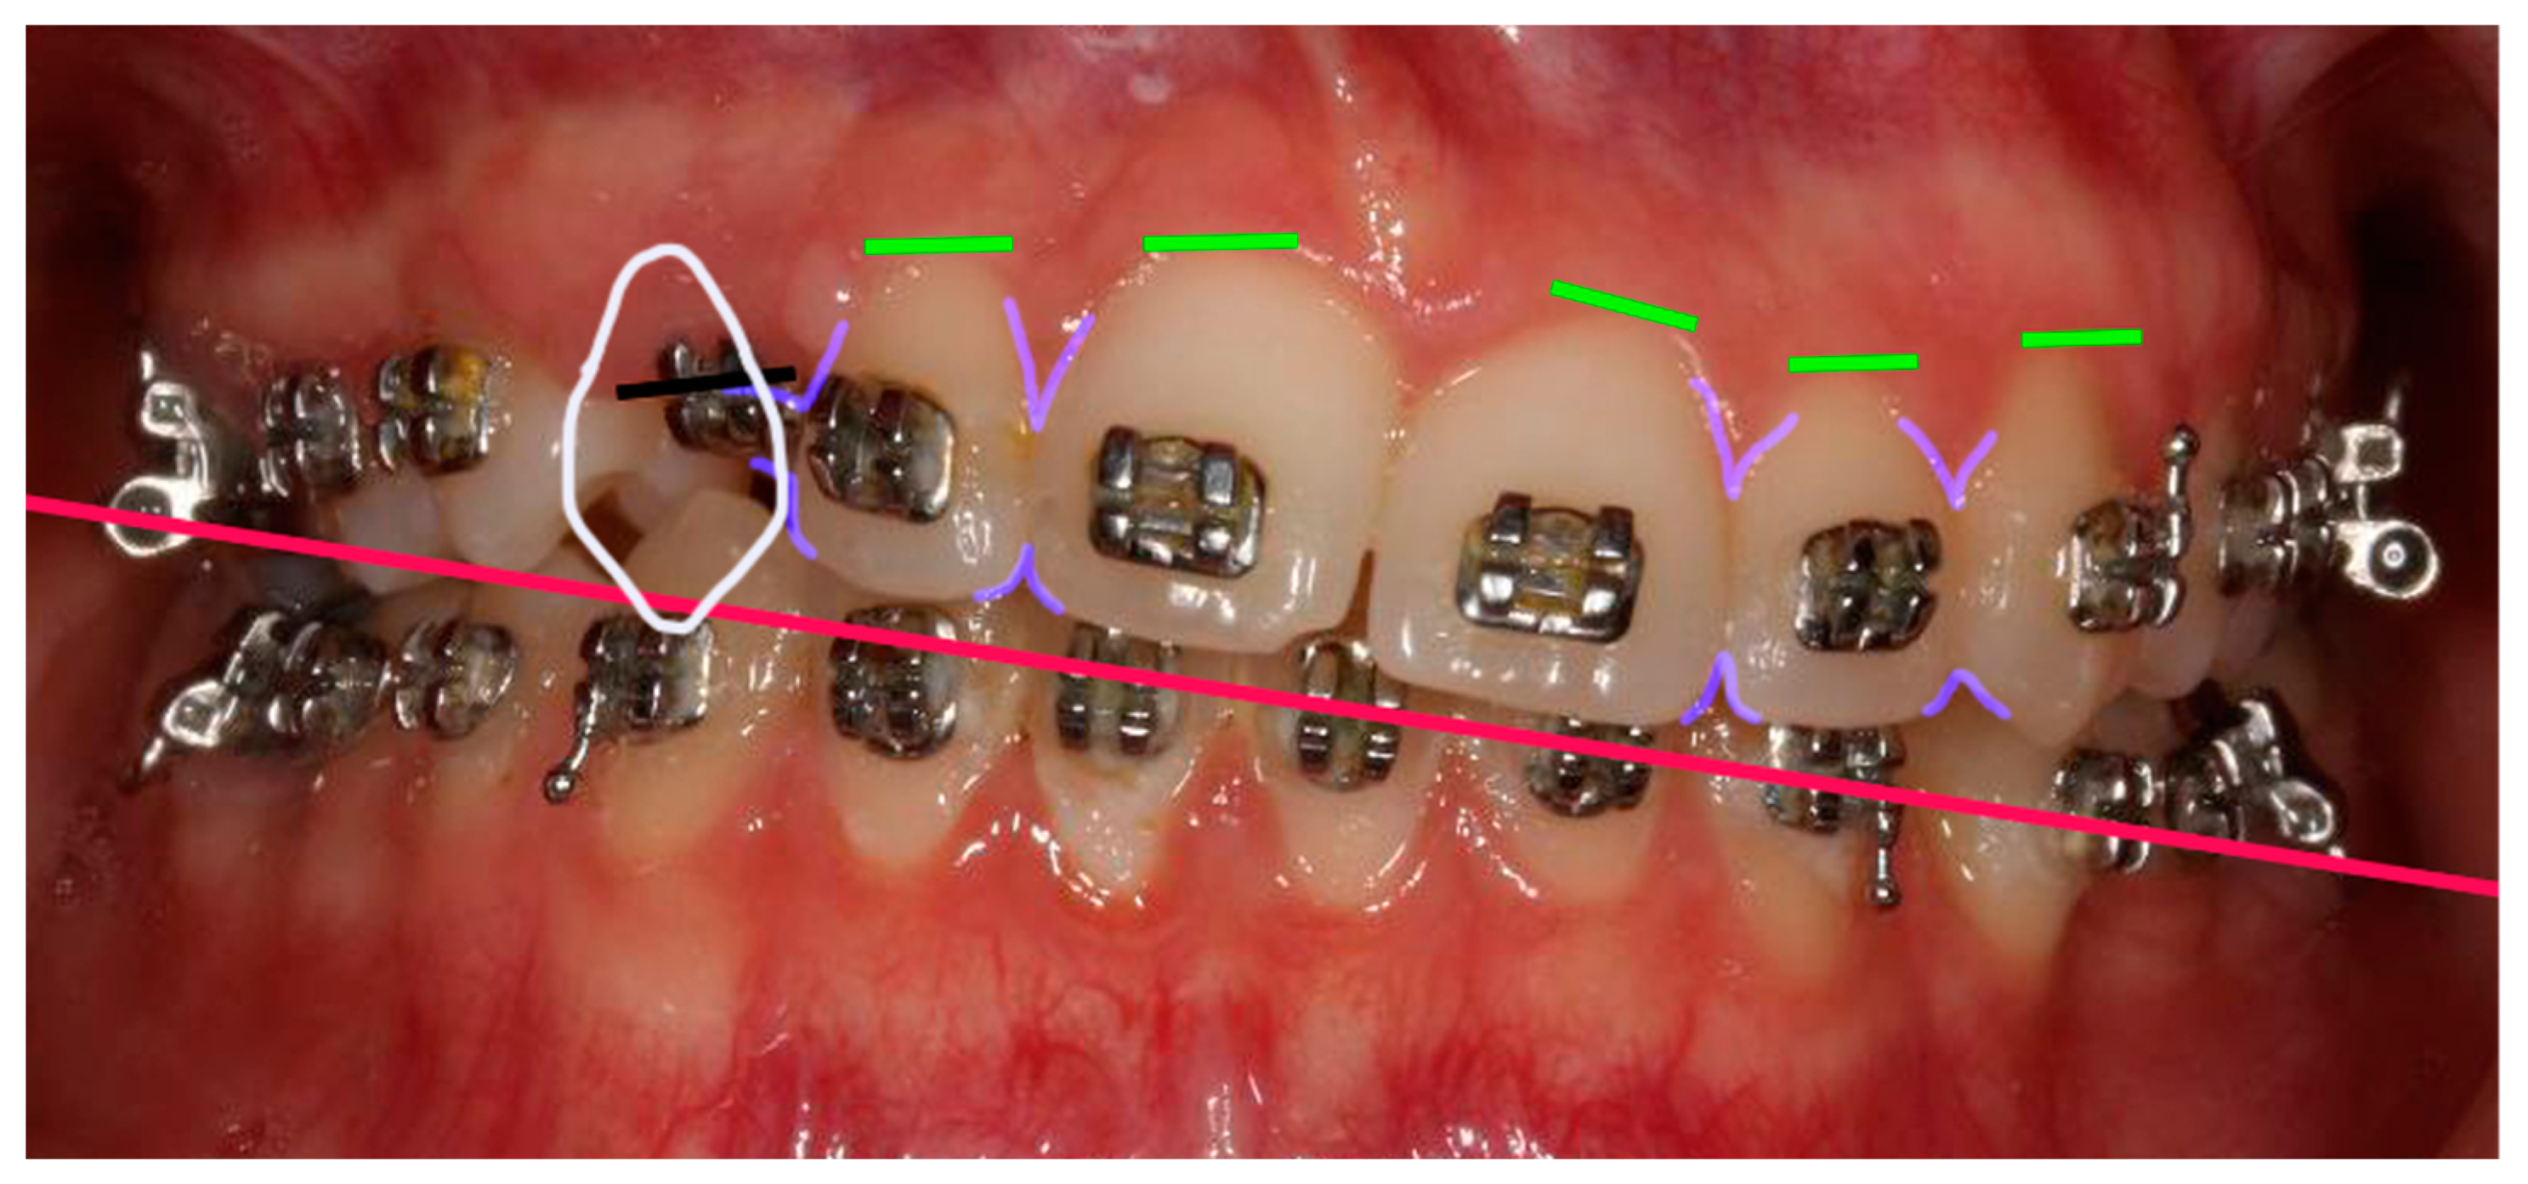

Figure 4. Smile Design. In white, shape of # 23 in position of # 13: the mesio-distal space available for the # 13 tooth is considerably larger than the mesiodistal size of # 23. In lilac, gingival and cervical embrasure spaces: there are considerable discrepancies in the embrasures’ form in the vicinity of # 13. In green, gingival zenith of the anterior teeth showing considerable alignment discrepancies. In red, aesthetic plane, clockwise canted.

A Photoshop Smile Design (PSD, Adobe Photoshop, Adobe, Saint Jose, California, CA, USA) [8] was presented to the patient (Figure 4). The patient was informed of the limitations associated with the present treatment, particularly regarding the aesthetic outcomes. Indeed, the reduced size of the papilla between # 12 and the future # 13, in conjunction with the bone level of the edentulous ridge apical to the cementoenamel of # 12, could have resulted in the persistence of a black triangle. The different mesio-distal diameter of teeth # 13 and # 23 was also considered.

At the same time, a new PSD was performed in the teeth’s final position (Figure 5). Analysis of the smile revealed asymmetry in the cervical and occlusal embrasures between teeth # 12 and # 22, as well as width discrepancies between the mesio-distal width of teeth # 13 and # 23. Indeed, the mesio-distal width of # 13 was larger than the mesio-distal width of # 23. According to the PSD, to enhance the harmony of the patient’s smile, a composite restoration of tooth # 12 could be proposed, focusing on improving the distal transition line, while also enhancing the mesio-distal width discrepancy between the canines. Given the periodontal condition of # 12, this restoration could also help minimise the black triangle between teeth # 12 and # 13.